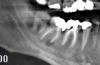

zybnaya feya Опубликовано 18 декабря, 2010 Поделиться Опубликовано 18 декабря, 2010 (изменено) Удаление 48 и реэндо 47,46,эндо 44,45 Изменено 18 декабря, 2010 пользователем zybnaya feya Ссылка на комментарий

stom13 Опубликовано 19 декабря, 2010 Поделиться Опубликовано 19 декабря, 2010 Удаление 48 и реэндо 47,46,эндо 44,45+1 Ссылка на комментарий

silver77 Опубликовано 20 декабря, 2010 Поделиться Опубликовано 20 декабря, 2010 Удаление 48 и реэндо 47,46,эндо 44,45поддерживаю Ссылка на комментарий